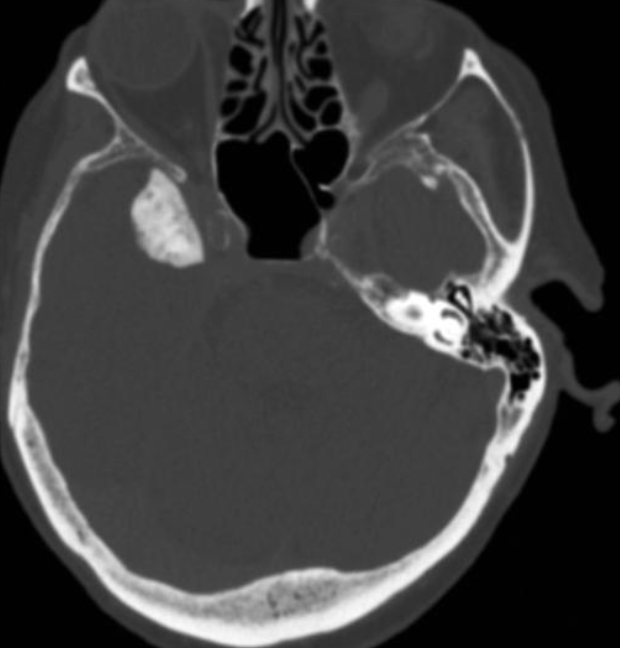

This sagittal T1-weighted MR image shows a suprasellar lesion in a 12 year-old boy. There is a fat-containing area and a cystic area. There was minimal soft tissue component. The lesion expanded and remodelled the sella, without bone erosion. There is elevation of the optic chiasm, and the pituitary can be seen compressed into the base of its fossa.

Case Discussion

The lesion was biopsied. There were epithelial elements, underlying connective tissue with sebaceous glands, and fat, consistent with a mature teratoma. There were no immature or malignant components.

Intracranial teratomas are midline tumours which may contain calcium, soft tissue, cysts and fat. They occur from the optic chiasm to pineal regions. They may be mature, immature or malignant, depending on the degree of differentiation. Differential diagnoses include craniopharyngioma, dermoid and non-germinoma germ cell tumour.